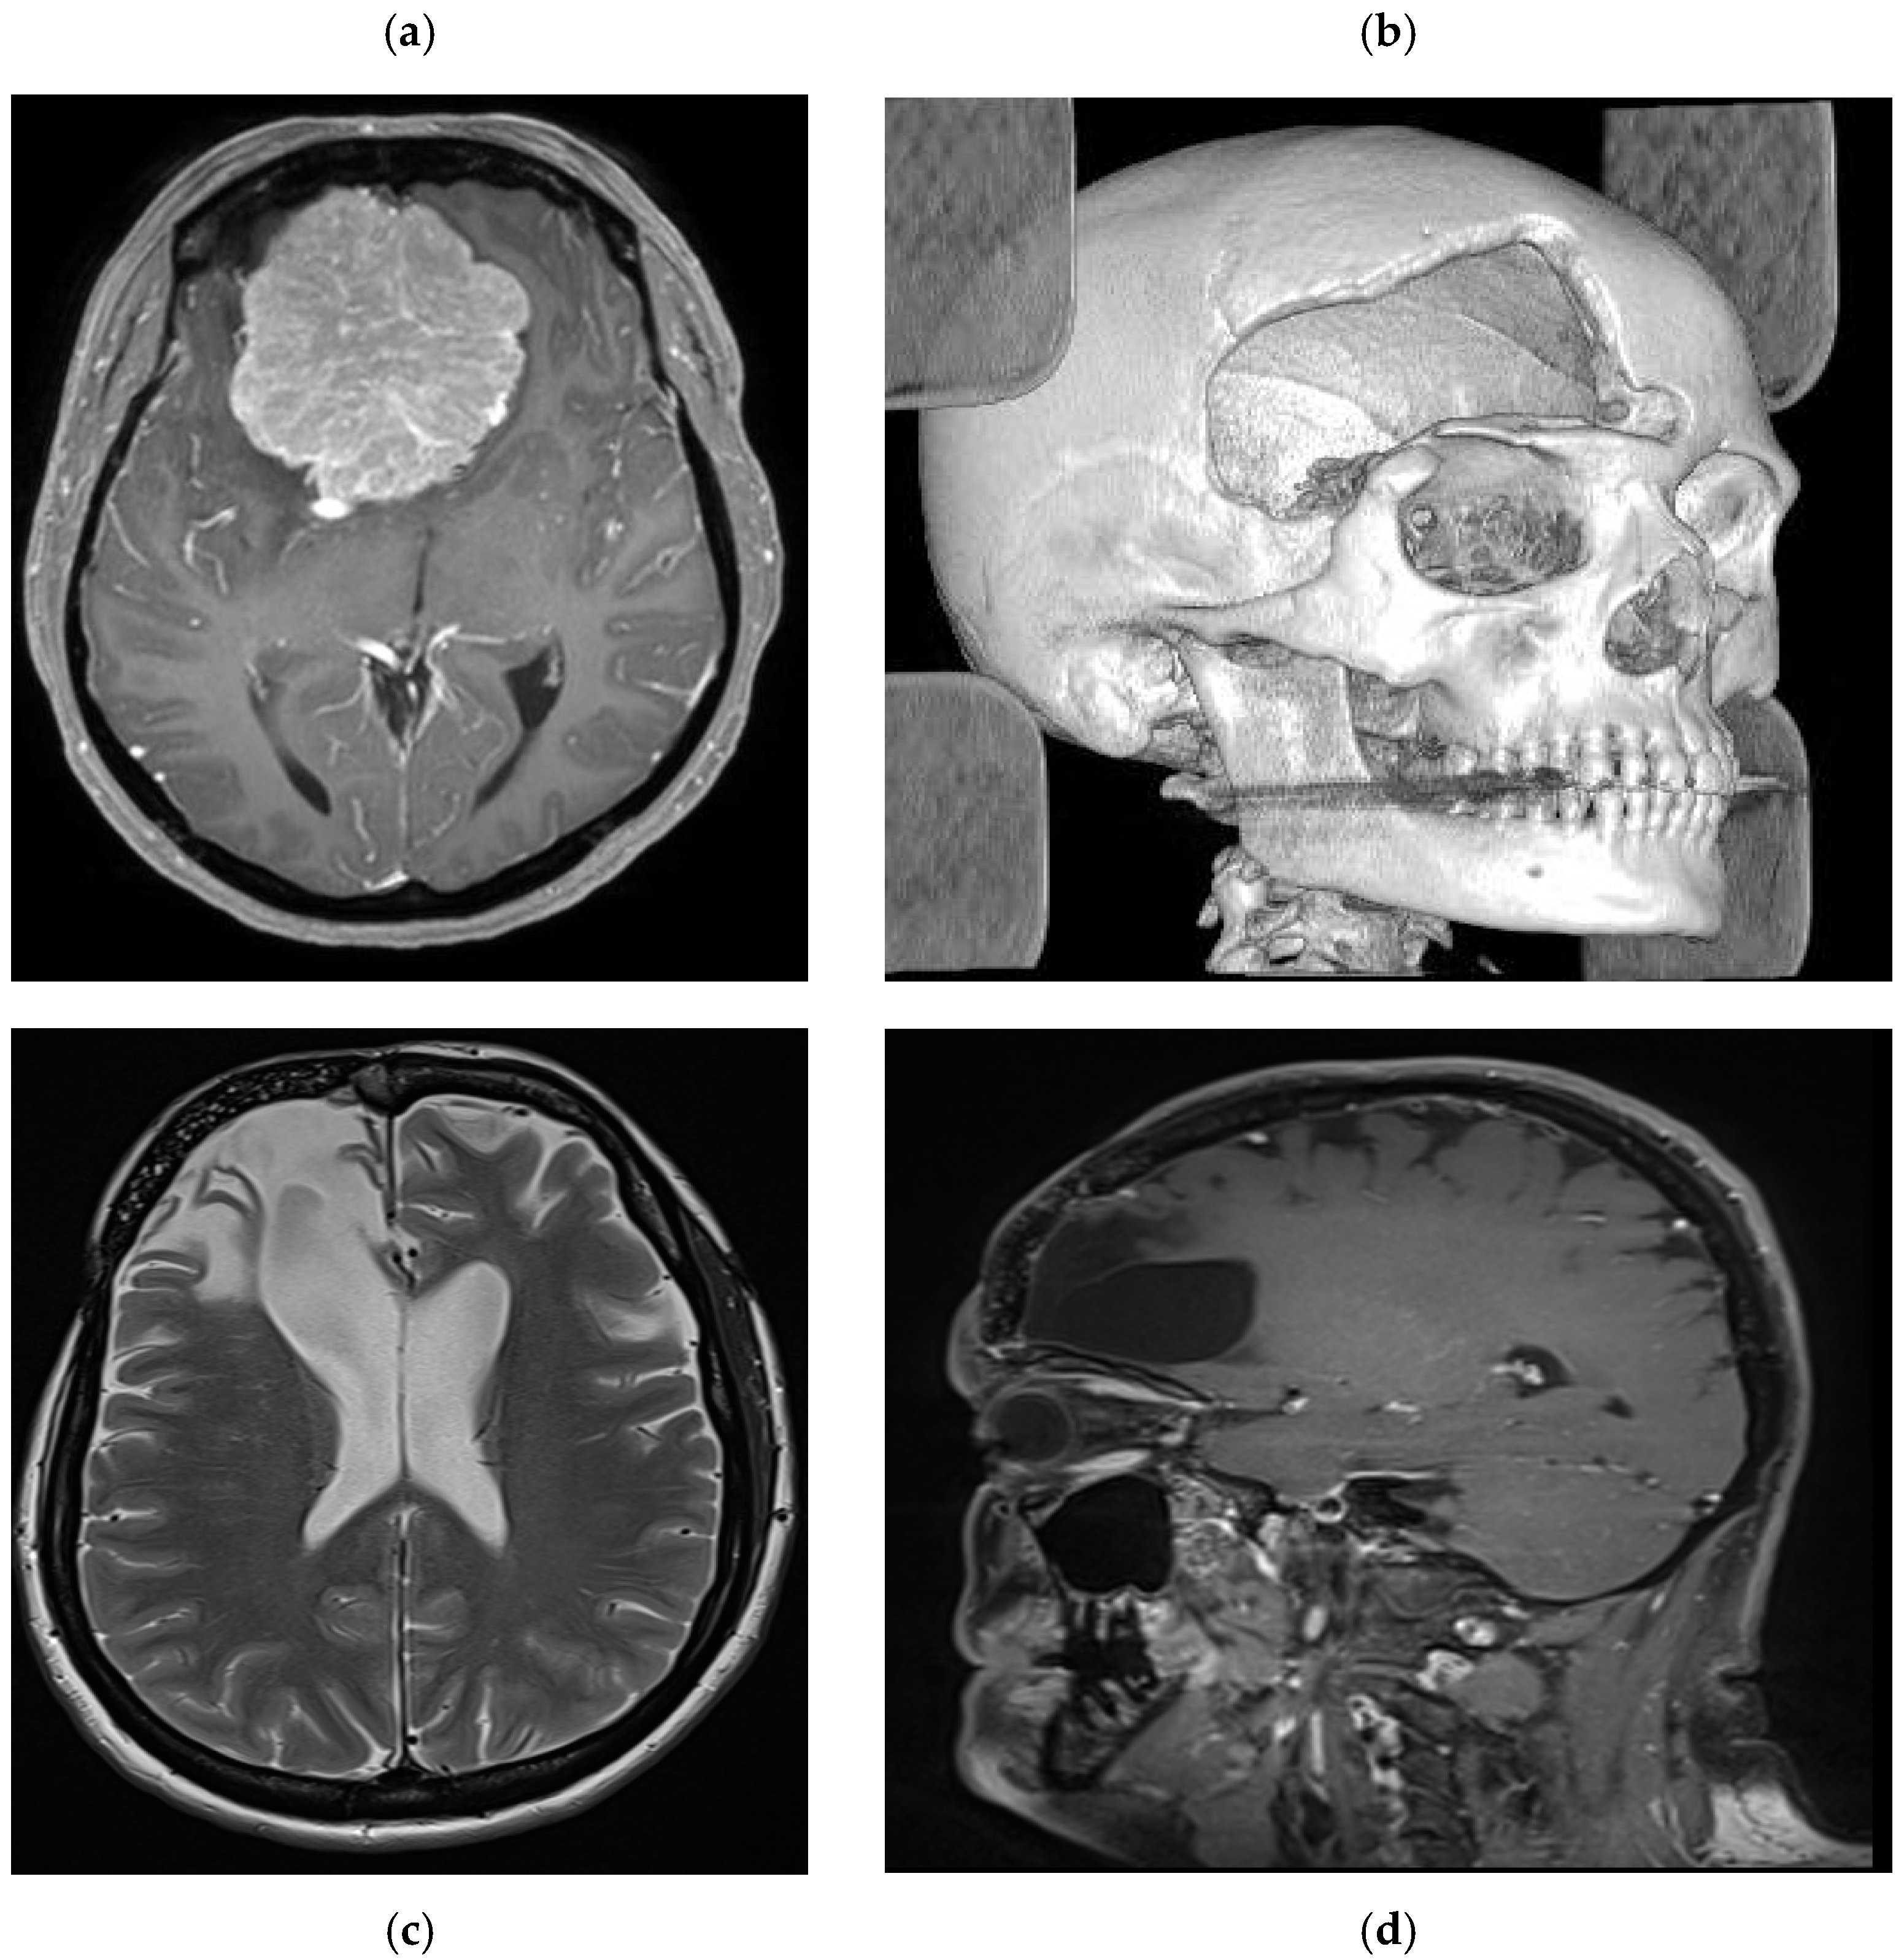

Patient number 1 is a 48-year-old female who underwent surgery for a large olfactory groove meningioma using a right frontotemporal craniotomy (Figure 3). One month later, she underwent reoperation following postoperative infection (frontal sinus cranialization and bone flap removal). Intraoperative samples were positive for S. epidermidis, and she received appropriate antibiotic treatment for 6 weeks. Due to the location of the bone flap, a custom-made prosthesis was proposed to the patient to achieve the best aesthetic result. Once the treatment was completed, a fine-cut CT scan was performed to plan the 3D custom bone prosthesis, which was implanted 2 months after the end of the treatment. The aesthetic result was satisfactory, with no visible bony gap and good frontal symmetry. Long-term radiological follow-up was performed due to the risk of meningioma recurrence. At 5 years, no signs of fracture or displacement were observed (Figure 3), and a satisfactory aesthetic result was reported (Figure 4).

Figure 3. Case example MR images. (a) preoperative axial T1 weighted with gadolinium showing a large olfactory groove meningioma. (b) postoperative CT scan with 3D reconstruction showing a large aesthetic defect in the right frontal region. (c) Postoperative axial T2 weighted and (d) T1 weighted sagittal images with gadolinium showing the prosthesis perfectly fitting the cranial defect with imaging artifact.

The Cranial Loop system offers an innovative alternative by providing stable, non-metallic fixation without need for additional instrumentation. The findings of this study confirm the safety and efficacy of the Cranial Loop system for PHA prostheses fixation. No intraoperative complication was encountered, and all patients achieved stable long-term outcomes without prostheses displacement. Furthermore, the absence of imaging artifacts facilitates postoperative surveillance, making the Cranial Loop™ system particularly advantageous for patients requiring long-term follow-up with MRI (Figure 3).